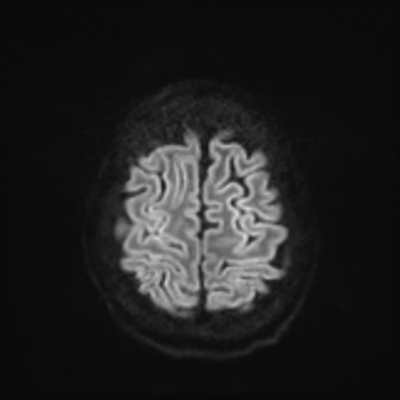

MRI brain (DWI)

You can clearly see diffuse cortical and basal ganglia diffusion restriction, and that of his deep cerebellar nuclei as well. The right occipital lobe abnormalities are a little more prominent, but then you remember that he is known to have had a right occipital stroke weeks ago.

In reviewing his data, you know that he doesn't have any of the strong predictors of a poor neurologic prognosis. However, based on these findings on MRI, along with the absent reactivity on cEEG, you are able to tell the primary team and the patient's family that he is likely to have a poor prognosis, based on these multiple moderate predictors. Recovery is not completely impossible-- there is more uncertainty with this prognostication than if we were able to get SSEPs-- but you're very worried about his outlook and that any potential recovery would require a very protracted rehabilitation period. Given his high cervical cord injury level, tracheostomy would be required anyway. So, it comes down to whether his family thinks he'd want to pursue these aggressive measures.